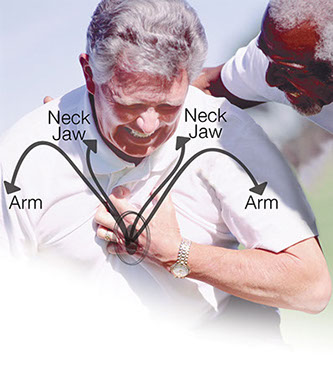

Heart Attack Warning Signs

For any heart attack warning sign, call 9-1-1 or your local EMS.

Common Heart Attack Warning Signs

* Feeling of pain (may spread to the arm, neck, jaw, tooth, or back), tightness, burning, squeezing, fullness, or heaviness in the chest that lasts more than a few minutes or goes away and comes back

* Chest discomfort with fainting, shortness of breath, lightheadedness, nausea, or sweating. Unusal chest, abdominal, or stomach pain.

* Dizziness, nausea, trouble breathing, or arm or jaw pain without chest pain

* Fast or uneven heartbeat or pulse; sweating for no reason; or pale, gray, or clammy skin

Signs More Likely to Occur in Women

* An uneasy feeling in the chest with any problem listed above or with: Unexplained or extreme anxiety; unusual fatigue or weakness; fluttering hearbeats; or severe indigestion that does not go away with an antacid